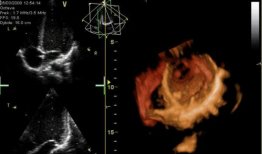

心脏跳动视频,揭秘心脏跳动的奥秘

你知道吗?最近在网上看到一个超级神奇的视频,简直让人心跳加速!就是那种心脏跳动的视频,感觉就像是在你的胸腔里亲自感受一样。今天,...

2025-07-14 164 -